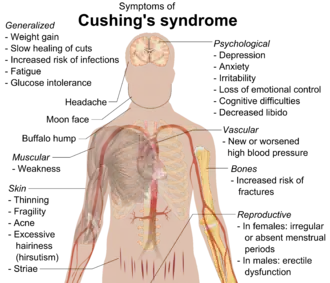

Symptomen

- Typische vetverdeling: vetopstapeling ter hoogte van de buik (centrale adipositas), terwijl de armen en benen slank zijn en soms zelfs mager door spierafbraak.

- Gewichtstoename. Door de ongewone vetverdeling over het lichaam lijkt iemand ook veel dikker.

- Moonface (letterlijk 'maangezicht'), een rond opgeblazen gelaat

- Bisonnek (ook wel 'buffalo hump' genoemd), een bochel van vet hoog op de rug

- Dunnere huid, waarbij er sneller dan normaal blauwe plekken ontstaan

- Striae (zwangerschapsstrepen) op buik en billen door gewichtstoename en verzwakking bindweefsel.

- Vermoeidheid

- Slaapproblematiek, waarbij het dag-nachtritme moeilijk is te handhaven.

- Dunner wordende spieren (spieratrofie) en vermindering spierkracht

- Dunner en brokkelig wordende haren

- Vaak moeten plassen (polyurie)

- Te hoog cortisol in het bloed. Het cortisol kan ook in het speeksel en de urine gemeten worden.

- Overmatige acne

- Hypertensie (hoge bloeddruk)

Bij vrouwen

- Verminderde vruchtbaarheid of verminderd libido.

- Toename van haargroei (hirsutisme) op gelaat, borsten, buik en ledematen. De menstruatie kan onregelmatig worden of zelfs helemaal uitblijven.

Bij mannen

- Verminderde vruchtbaarheid, verminderd libido en/of impotentie.